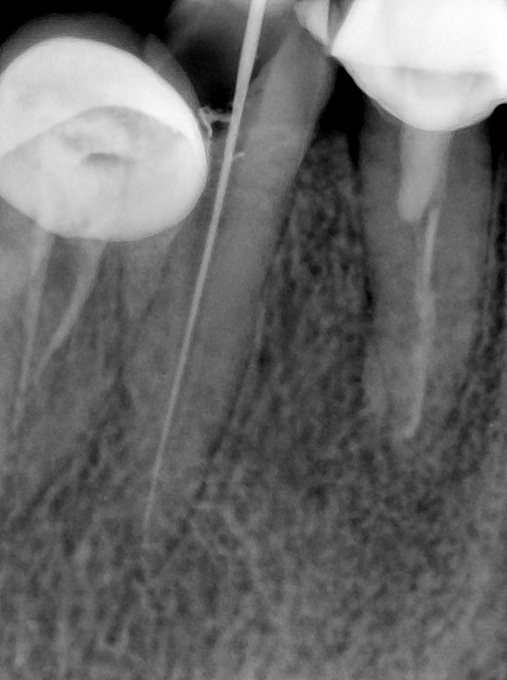

CR/DR 牙齿分割阶段记录

当前进展

- 完成了 CR/DR 牙齿相关分割训练

- 当前结果已经达到阶段预期,但仍有细节问题需要继续处理

相关测试

遇到的问题

- 训练过程中出现过 mask 下移问题

- 部分结果会出现 box 填充异常

- mask 边缘仍然有比较明显的锯齿感

第二版算法问题测试